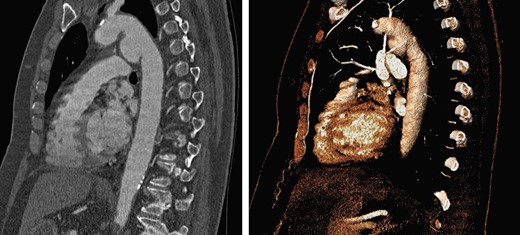

A 74-year-old woman was referred to our vascular service with a 6-month history of hoarseness of voice and intermittent dry cough. The patient’s medical history included hypertension and gastroesophageal reflux disease. Flexible laryngoscopy demonstrated a foreshortened, lateralised and flaccid vocal fold consistent with unilateral vocal cord paralysis. Subsequent computed tomography (CT) imaging of the neck and thorax revealed a saccular aneurysm in the aortopulmonary window measuring 39 mm (Fig. 1). Digital subtraction angiography confirmed the presence of a ductal aneurysm with a well-defined neck and no intraluminal thrombus (Fig. 2). There was no contrast extravasation into the mediastinum or pulmonary circulation. Following a cardiovascular multidisciplinary meeting, treatment options were discussed with the patient and consensus favoured endovascular repair. The distance from the proximal margin of the aneurysmal neck to the origin of the left subclavian artery measured just under 2 cm and therefore did not meet the manufacturer’s minimal landing zone requirements. To circumnavigate this dilemma, a left subclavian stent graft was inserted with its proximal end parallel to the main thoracic endoprosthesis. The procedure was uncomplicated and repeat imaging revealed widely patent stent grafts with satisfactory positioning and absence of endoleak (Fig. 3). Our patient was discharged home on the second postoperative day. She continued speech and language therapy postoperatively and has made remarkable recovery of phonation, declining any further treatment options for same.

Sagittal CT with 3D reconstruction at 1-year post-intervention, showing satisfactory placement of stent grafts.